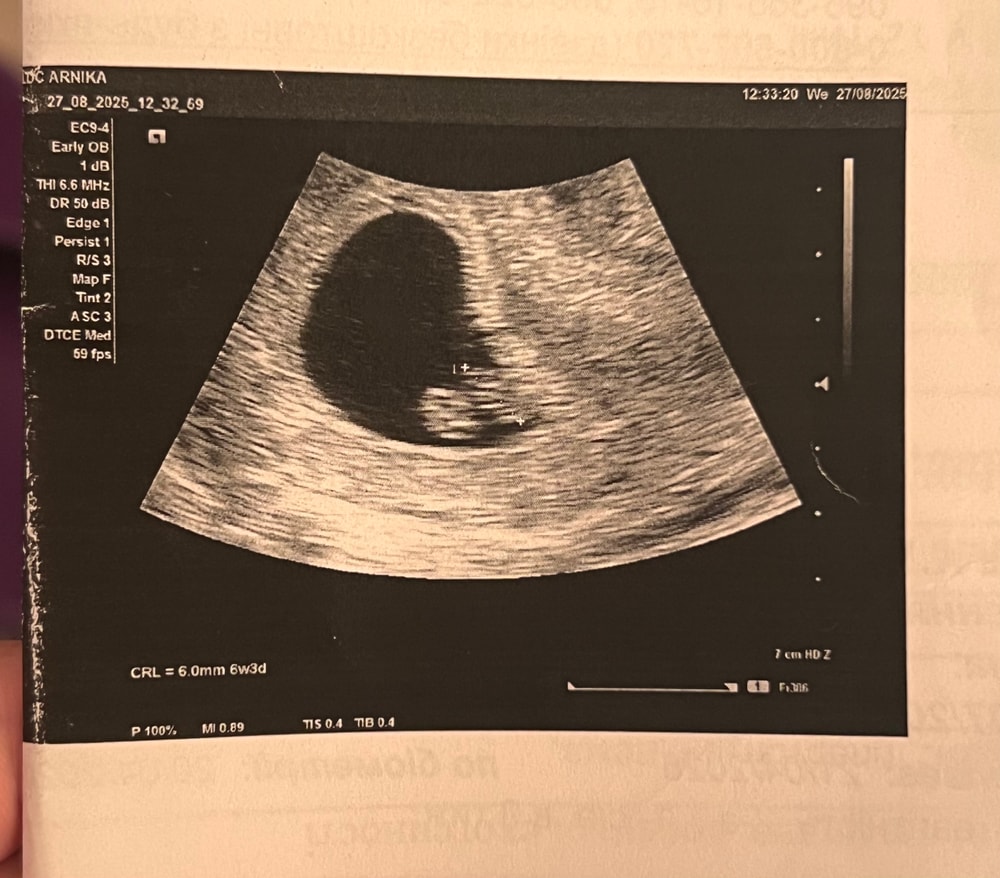

Второе узи 6 недель 3 дня

На прошлом узи в ровно 5 недель увидели только ПЯ 6 мм и ЖТ15 мм, увидели гипертонус матки и поставили отставание по сроку. Сегодня были у другого врача, она сказала что малыш развивается чудесно, увидели и эмбриончик 6 мм и желточный мешочек 3,6мм, в общем плодное яйцо 22мм. Желтое тело в левом яичнике увеличилось до 20мм. Срок по узи и по месячным совпал😌

даже увидели как бьется сердечко, 111 ударов в минуту🥰 тонус прошел)